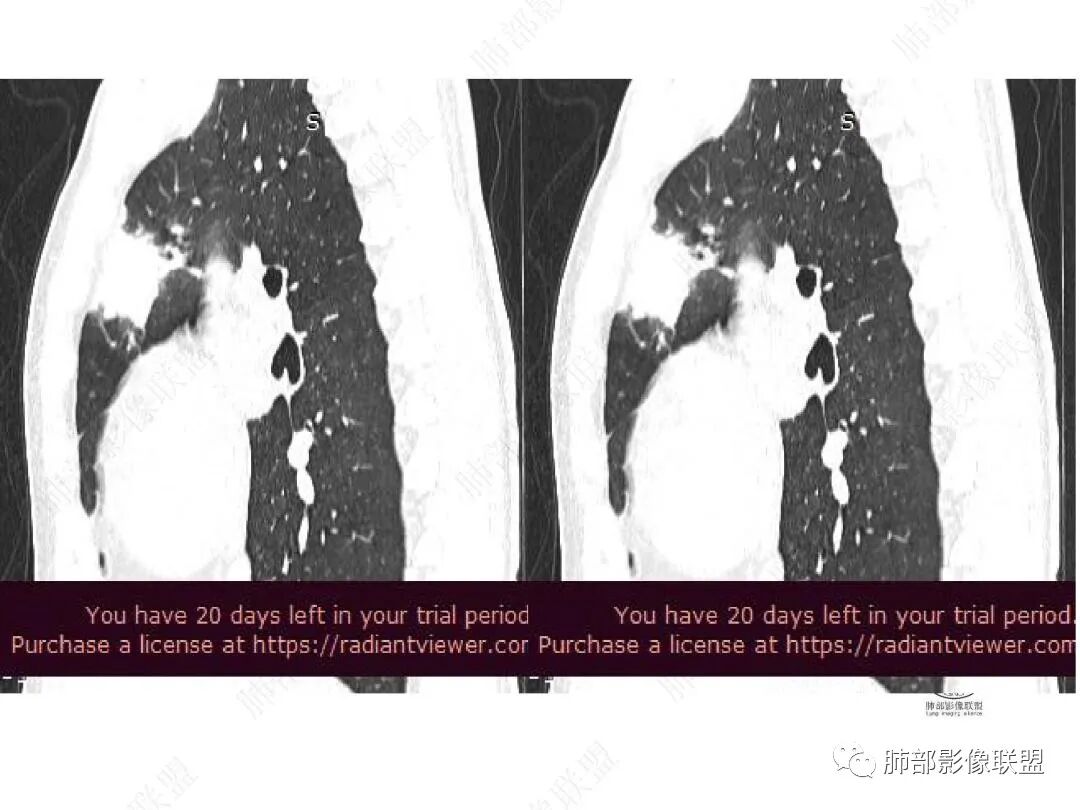

1年2个月图像变化:

右上叶前段胸膜下新发病灶;纵隔淋巴结较前增大

边缘平直,有锯齿状影

支气管进入其中,中近端堵

远端见斑片状高密度影

强化与肌肉类似,纵隔淋巴结强化类似

与胸膜关系:糊墙

2.右肺上叶纵隔旁新发实性密度病灶,密度均匀,轻度强化,未见空洞、液化坏死及钙化,血管穿行自如,支气管进入后狭窄截止。灶周磨玻璃影边界不清,病灶未见明显分叶毛刺,平直、轻度收缩、周围偶见结节影,但未见树芽征。注意纵隔胸膜侵入或突入比较明确。纵隔淋巴结轻度增大。

3.右肺容易想到的病变有慢性炎症、IGg4相关、新生物(炎性肌纤维母细胞瘤、腺癌等)。但病灶侵入纵隔胸膜应当更符合恶性肿瘤。病程进展及强化等影像特点不支持继发性肺结核。